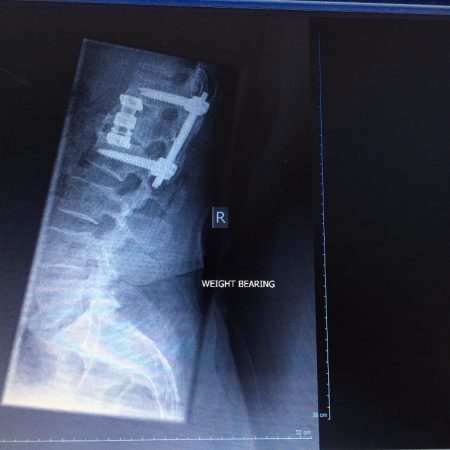

The First Rule of Back Club Part III

16th June 2017 · Posted by Philip Cavell

Phil's Journal five weeks post spine-fusion surgery. It is the first steps on a long road back. But for the first time in five years his spine appears to be straight.